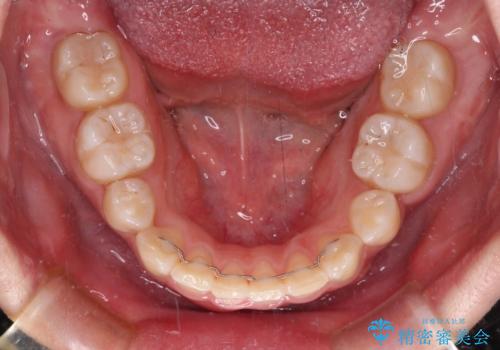

著しい過蓋咬合の改善が必要であった割には、治療期間は2年強と標準的でした。

八重歯は3,4か月で速やかに改善されました。